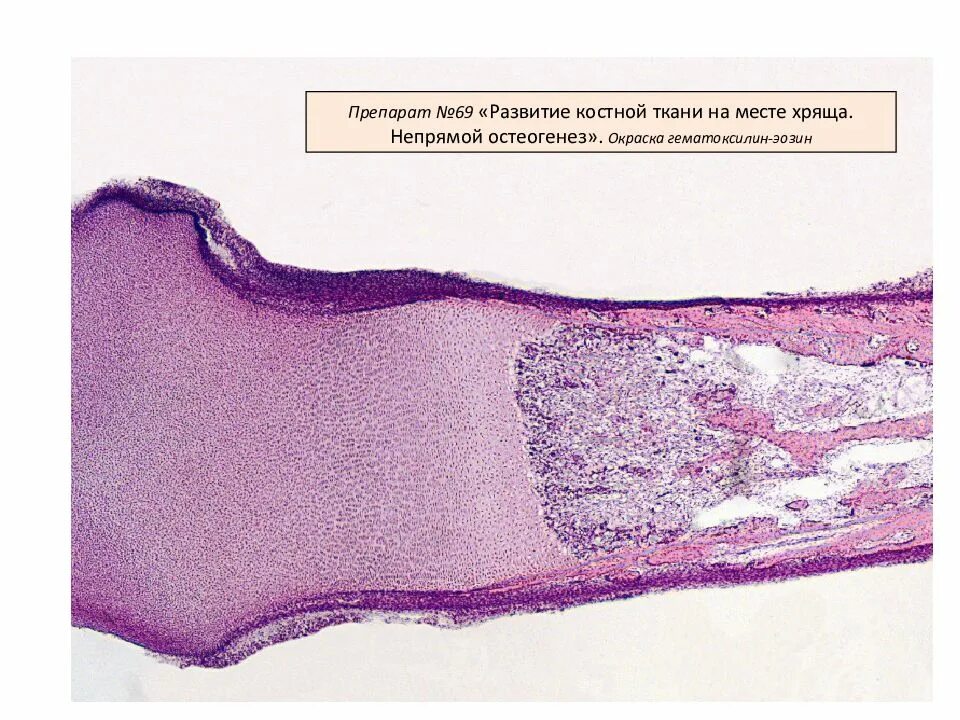

Развитие хряща гистология